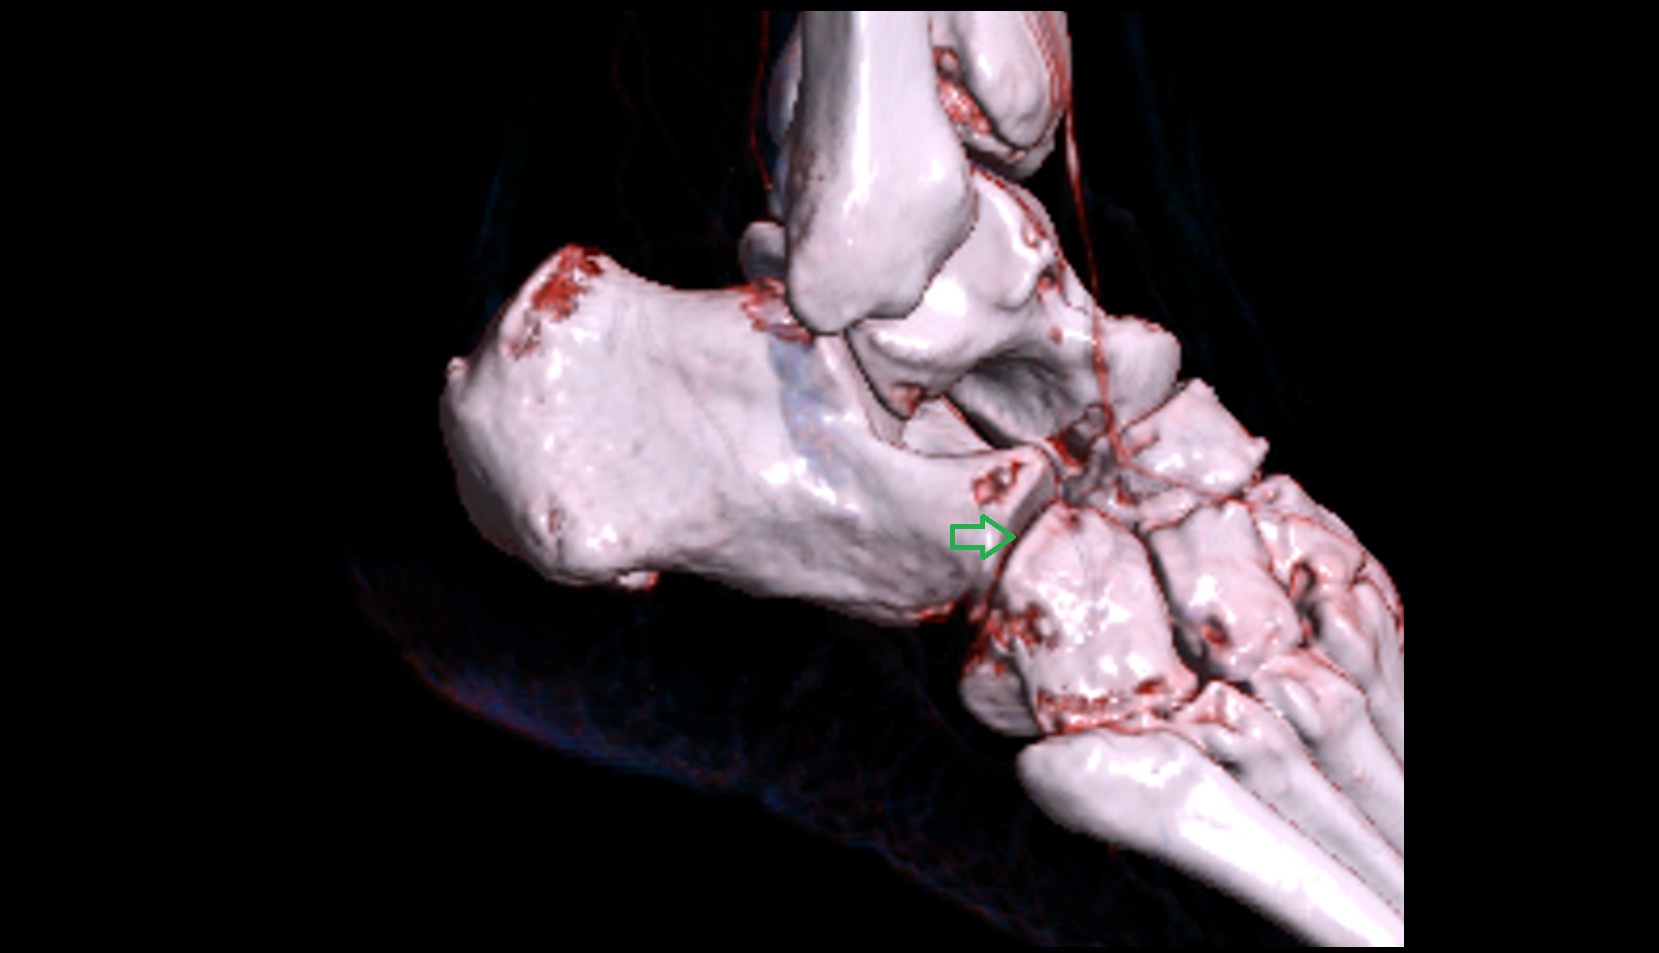

- Talus

- Head of talus

- Body of talus

- Neck of talus

- Calcaneus

- Anterior process of calcaneus

- Sustentaculum tali

- Cuboid

- Ankle joint

- Talocalcaneal joint

- Talocalcaneonavicular joint

- Calcaneocuboid joint